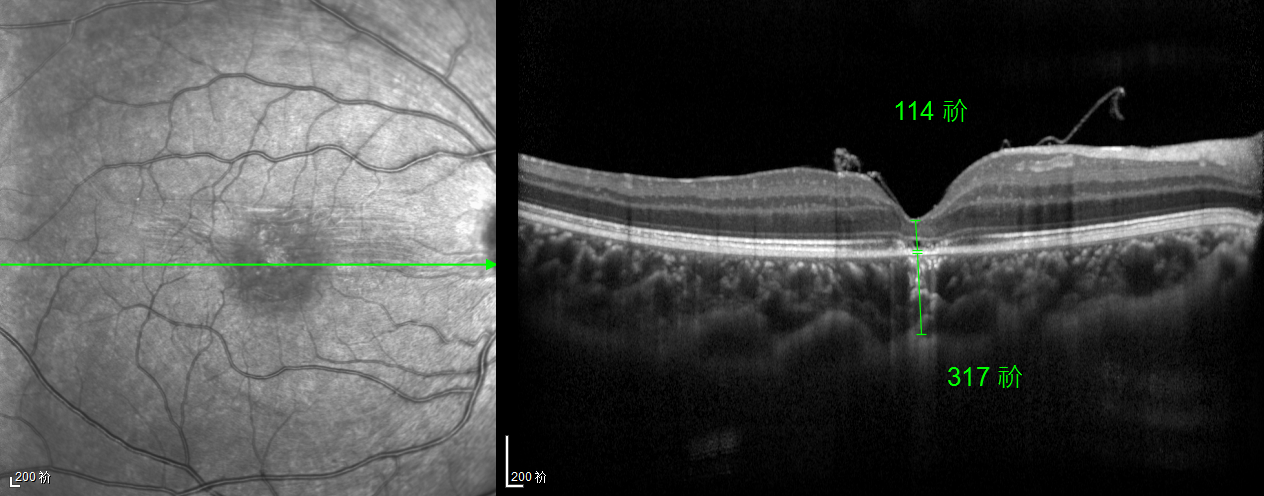

除此之外,利用自體組織覆蓋為黃斑裂孔提供了理想的愈合環(huán)境,裂孔閉合速度顯著快于傳統(tǒng)方法。誠(chéng)誠(chéng)接受手術(shù)24小時(shí)后,檢查可見(jiàn)內(nèi)界膜瓣位置良好;術(shù)后1個(gè)月,黃斑裂孔已經(jīng)閉合,視力恢復(fù)到0.5;術(shù)后兩個(gè)月,視力進(jìn)一步提升到0.7。

“書(shū)本的文字都變直了,黑板上的字也更清晰了!”

術(shù)后3個(gè)月復(fù)查時(shí),小男孩的眼睛閃耀著自信的光芒。